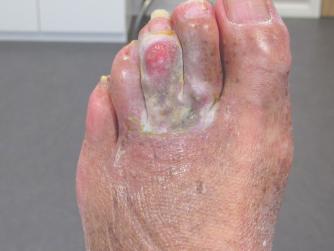

Begin februari 2024 had ik de laatste total-skin bestraling in Leiden en na zo'n 3 weken was ik gelukkig van de jeuk af op mijn hoofd, borst en buik. Maar helaas heb ik slechts een paar dagen kunnen genieten van een pijn en jeukvrije huid. Halverwege februari, toen de jeuk eindelijk weg was, begon de ellende met voeten en benen. Ook in het gezicht waren de verdikkingen weer goed te zien en de jeuk in het gezicht was ook weer terug. Wat een ellendige ziekte is en blijft het.

Na mijn laatste bezoek in het LUMC kreeg ik toch weer Ledaga voorgeschreven, terwijl de vorige keer Ledaga smeren helemaal niet goed was bevallen. Maar goed, je wil toch ook zalven smeren die moeten bijwerken aan het herstel. In het filmpje is te zien waar ik de Ledaga moet smeren en dat ik er best wel moeite mee heb is dan ook niet zo verwonderlijk. Momenteel zijn er weer diverse plekken op het lichaam die me een hoop ellende bezorgen. Plekken op armen en benen, mijn buik, schouders, rug, nek, het hoofd en in mijn gezicht, tja, overal waar haren groeien verschijnt de FMF óf komt deze weer terug.